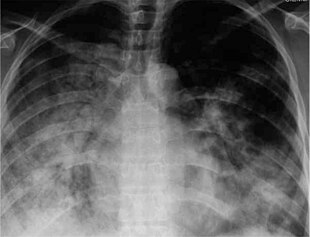

29 yr old with H1N1

There are a number of rapid tests for the flu. One is called a Rapid Molecular Assay, when an upper respiratory tract specimen (mucus) is taken using a nasal swab or a nasopharyngeal swab.[144] It should be done within 3–4 days of symptom onset, as upper respiratory viral shedding takes a downward spiral after that.[145]